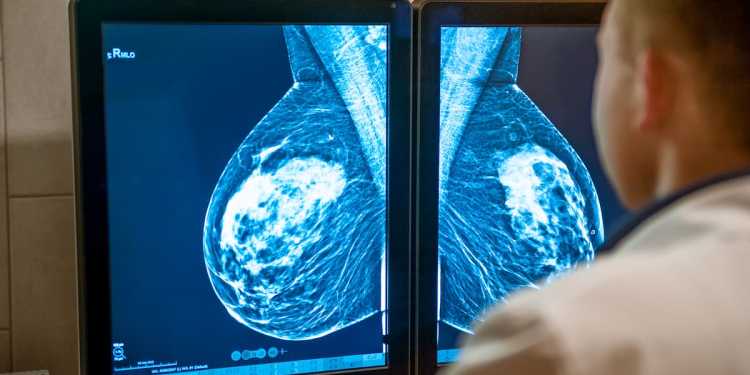

Women nationwide are experiencing breast implant ruptures during routine mammograms, leading to severe pain and potential costs of up to $22,000 for replacements. While Dr. Sally Urry from Health New Zealand acknowledges that such incidents are “extremely rare,” she notes that various factors, including implant age and type, contribute to the risk of rupture.